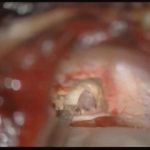

術中写真

摘出 前

摘出 中

摘出 後